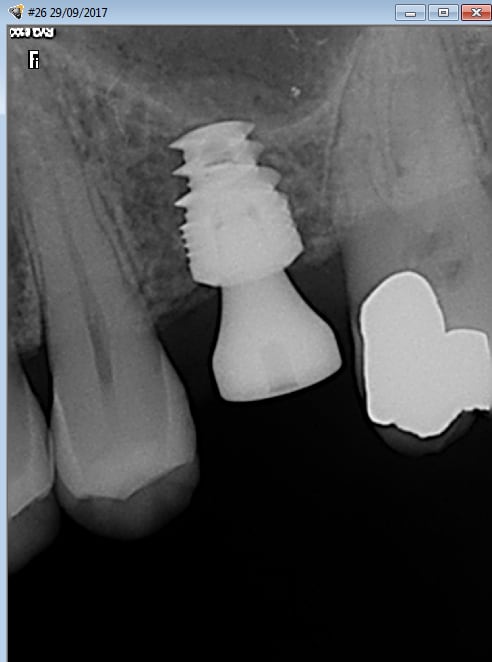

Les implants courts ça marche pas mal, ici un BICON 5x6 sur une 17 d'un confrère

--

Francis N.